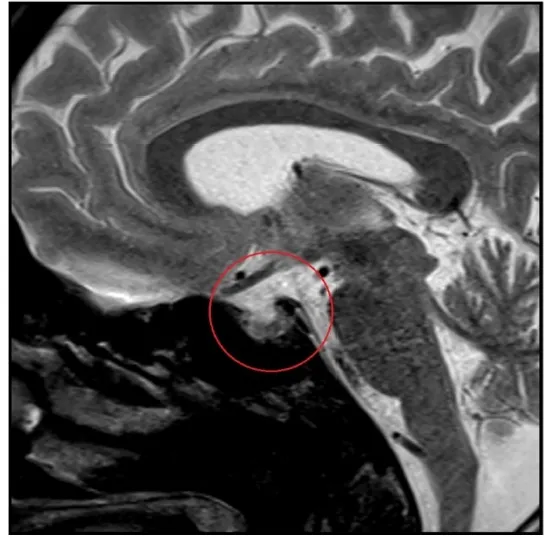

IRA + Icterícia: Um Caso que Exige Investigação Detalhada